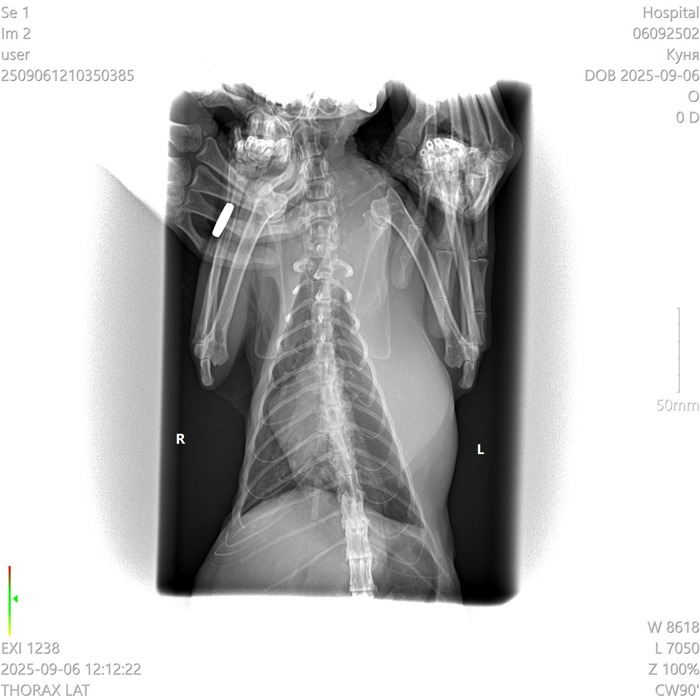

У кошки опухла левая часть грудной клетки.

Сделали рентген. Сказали что это не легкие, а какое-то новообразование. Что это может быть? У кошки тяжелое дыхание, почти не ест и не пьёт, приходится кормить через силу.